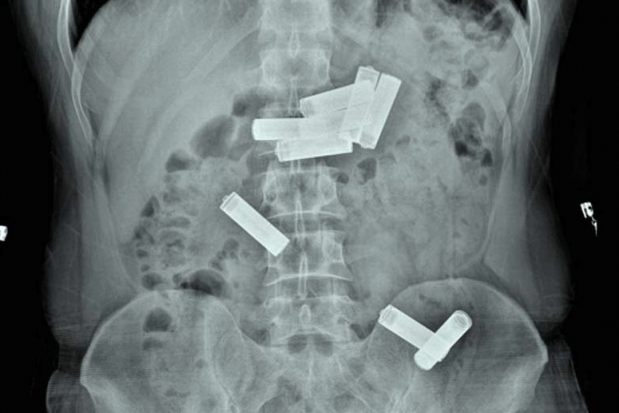

Gaziantep Kapalı Cezaevi'nde kalan  mahkum D.K., geçen hafta içerisinde koğuşunda rahatsızlanınca Dr. Ersin Devlet Hastanesi'ne götürüldü. Acil serviste muayenesi yapıldıktan sonra çekilen röntgende D.K.'nin  midesinde 8  kalem pil olduğu saptanınca Endoskopi Servisi'ne sevk edildi. Gastroenteroloji uzmanı doktor Ahmet Yağbasan başkanlığındaki ekip, yaptığı çalışma ile D.K.'nin midesindeki pillerin birisini çıkardı. Uzmanlar, mahkumun midesindeki diğer 7 pilin müdahale yapılarak çıkarılmasının dokulara zarar vereceğini belirleyince takip altında doğal yollardan çıkarılması kararını verdi. Bunun üzerine servise yatırılan D.K., 2 gün sonra midesindeki pilleri doğal yollarla vücudundan çıkardı.

"Vaka bize cezaevinden karın ağrısı şikayetiyle getirildi. Acil serviste çekilen röntgende midesinde kalem pillerin olduğunu belirledik. Bunun üzerine hastayı endoskopi ünitesine aldık. Midede 8 pil olduğunu gördük ve bunları özel aletlerle çıkarmayı denedik. Yaptığımız müdahale ile birini çıkardık ama diğerlerinin pozisyonu uygun olmadığı için çıkaramadık. Pillerin içindeki kimyasal maddelerden dolayı doku hasarına yol açabileceğini kanaat getirerek, hastanın diğer 7 pili takip altında doğal yollardan çıkarmasını kararlaştırdık. Serviste yatan hastamız 2 gün sonra pilleri doğal yollardan çıkarmış oldu."